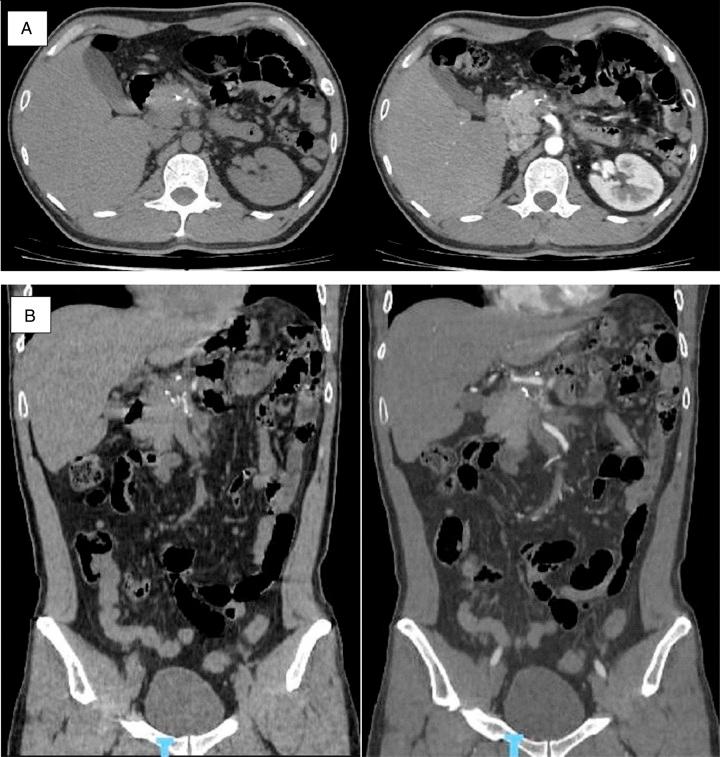

The authors present a clinical case of a 42-year-old patient who was diagnosed with MC 8 years ago, now admitted to the hospital with a palpable epigastric mass. Clinical and laboratory examinations showed consistent results for MC tumours, with metastasis to the body and tail of the pancreas and invasion of the splenic vein. Surgical resection and systemic screening were performed to ensure that there were no lesions elsewhere. Regular follow-up has found no localized lesions or complications after 15 months.

作者报告了一例临床病例,一名42岁患者8年前被诊断为MC,现因上腹部可触及肿块入院。临床和实验室检查结果与MC肿瘤相符,已转移至胰腺体尾部并侵犯脾静脉。进行了手术切除和全身筛查以确保其他部位无病变。定期随访发现15个月后无局部病变或并发症。

胰腺转移性骨骼外间叶性软骨肉瘤极为罕见。据我们目前了解,医学文献中仅记录了14例此类病例。胰腺转移的症状多样,转移性间叶性软骨肉瘤的影像学特征通常不典型。